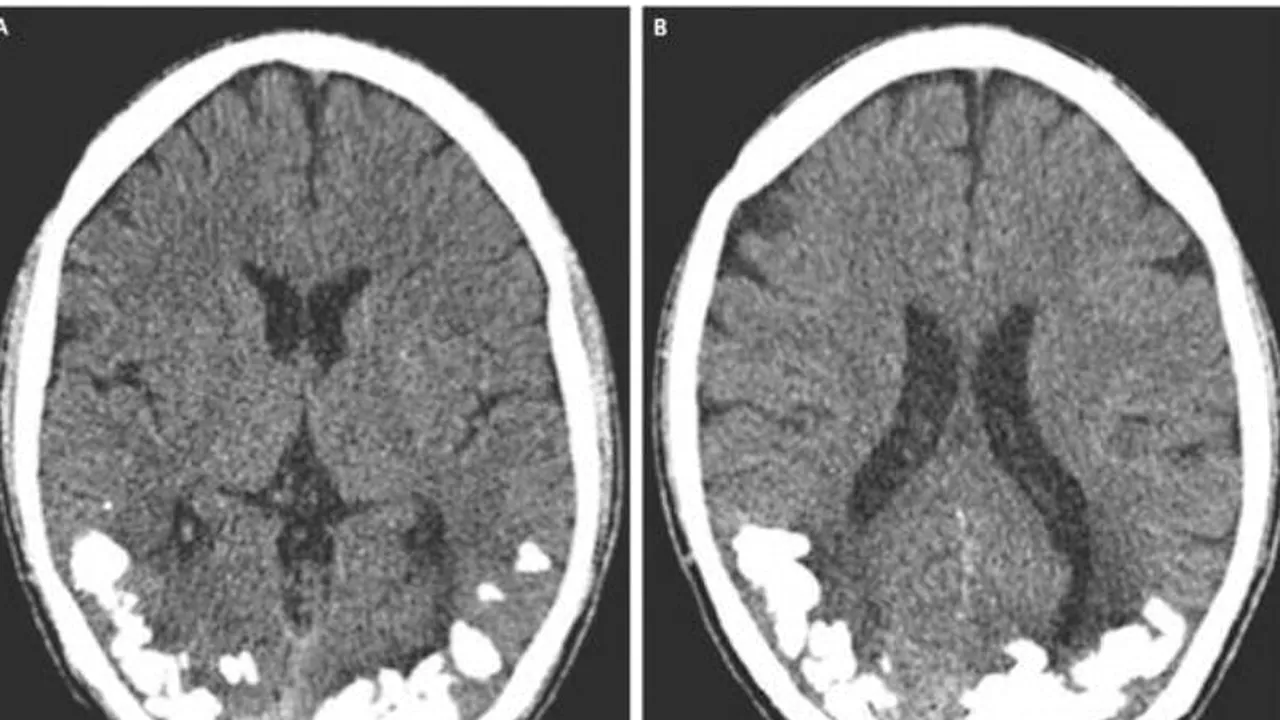

Un tânăr din Brazilia a ajuns la spital, după ce timp de 10 ani a suferit de migrene puternice și a avut probleme de vedere. Medicii au descoperit formațiuni calcaroase în creierul lui.

Medicii au descoperit în urma unei tomografii că în partea posterioară a creierul tânărului se formaseră de-a lungul timpului o serie de formațiuni calcaroase. Acestea se aflau chiar în regiunea unde se găseau nervii responsabili cu vederea, potrivit Live Science.

Rezultatele analizelor au arătat totodată, că bărbatul avea o deficiență de fier, toate acestea ducând la apariția formațiunilor din creier.

Medicii i-au recomandat brazilianului să urmeze o dietă lipsită de gluten și să ia suplimente cu fier și o serie de medicamente specifice epilepsiei . După începerea tratamentului starea bărbatului s-a ameliorat.